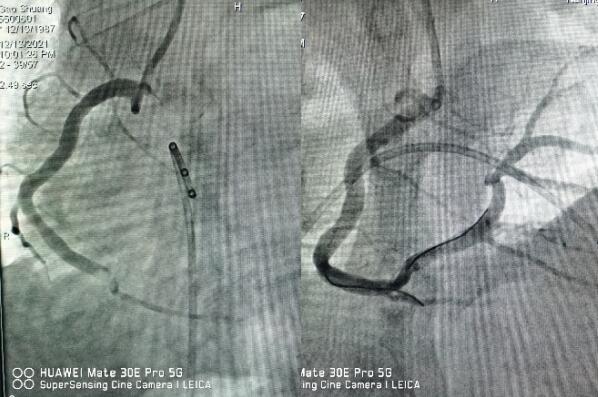

12月13日晚7點(diǎn)左右,一名32歲徐州在寧務(wù)工的男性患者,“突發(fā)胸痛1小時(shí)”來江寧中醫(yī)院就診,當(dāng)班醫(yī)師觀察到患者一般狀態(tài)極差,面色蒼白、大汗,

立即送入搶救室,測血壓92/60mmHg,心電圖提示急性下壁心肌梗死,三度房室傳導(dǎo)阻滯。

醫(yī)生立即予以搶救,并第一時(shí)間通知心內(nèi)科值班醫(yī)師,緊急啟動(dòng)綠色通道,全院相關(guān)科室全力配合,心內(nèi)科介入團(tuán)隊(duì)分工明確,迅速啟動(dòng)導(dǎo)管室。因患者心梗后并發(fā)嚴(yán)重心律失常,為了安全起見,造影前植入臨時(shí)起搏器,造影提示右冠狀動(dòng)脈急性完全閉塞,并成功開通血管,患者胸痛即刻緩解,目前正在康復(fù)過程中。